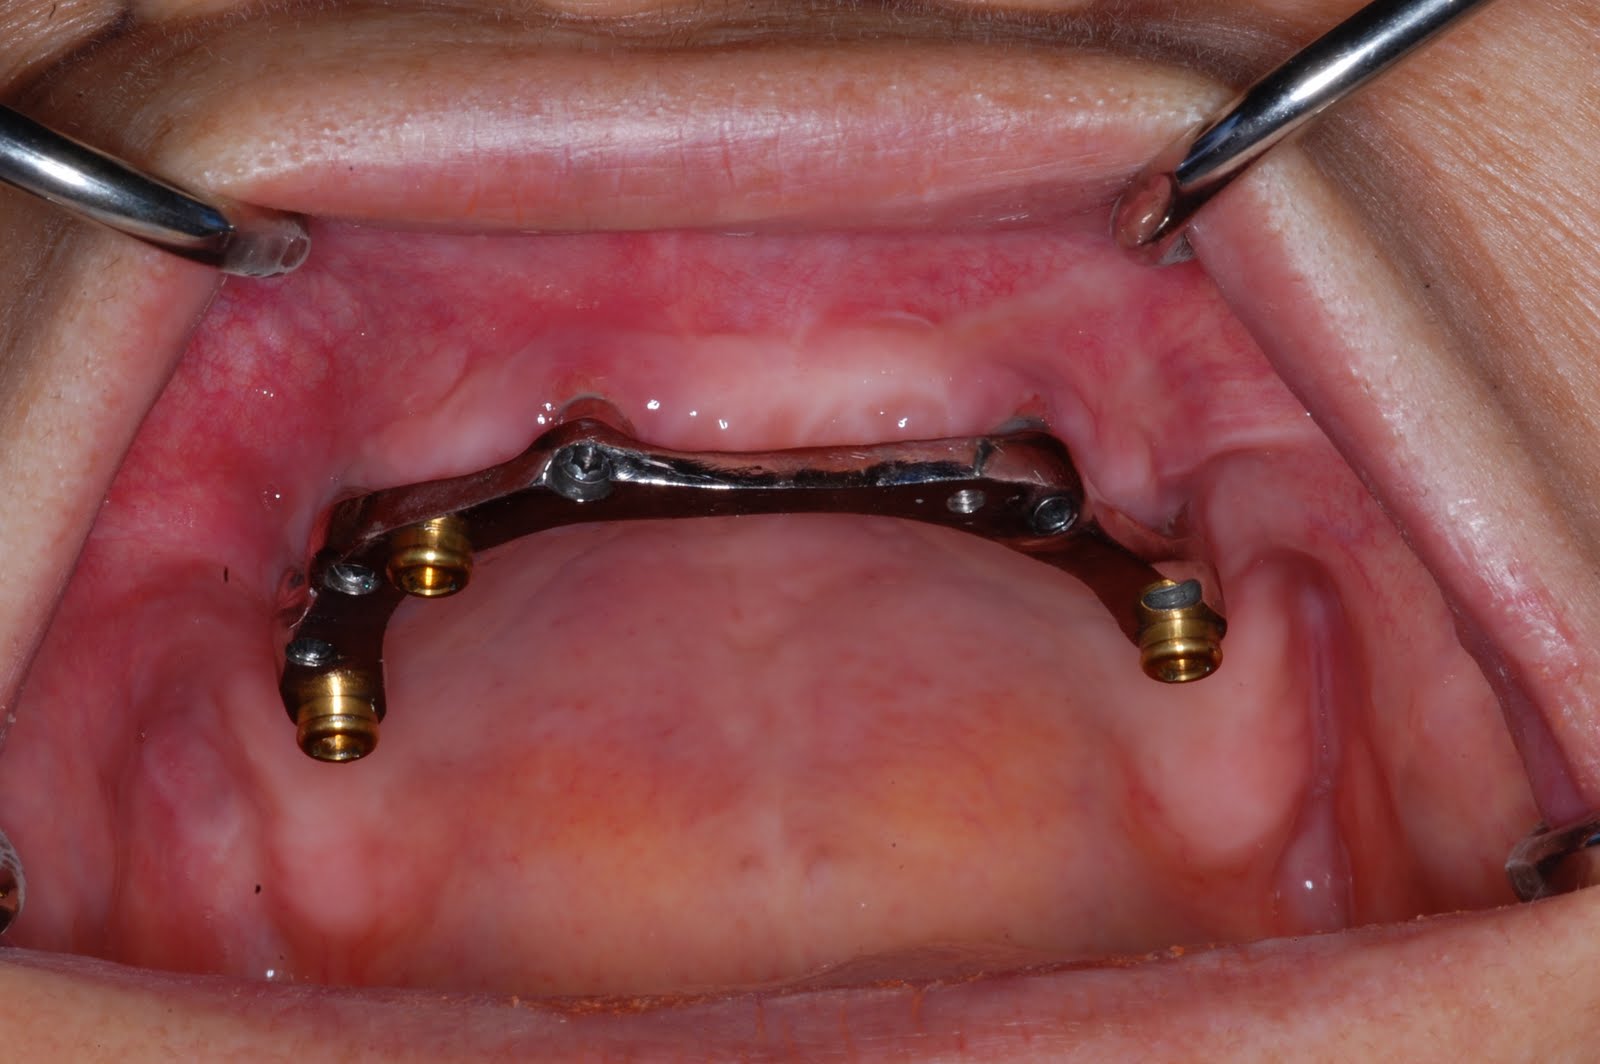

Maxillary implantsupported bar overdenture and mandibular implantretained fixed denture using Overdenture Maxillary therefore, this systematic review aimed to compare maxillary overdentures supported by four or six. an implant overdenture offers a stabilized removable solution for the edentulous maxilla, which provides increased patient. maxillary implant overdentures are a reliable treatment option for general dental practitioners, once competent with. therefore, this systematic review aimed to compare maxillary overdentures supported by. Overdenture Maxillary.

Attachment of clips in a barretained maxillary implant overdenture A clinical report Journal Overdenture Maxillary therefore, this systematic review aimed to compare maxillary overdentures supported by four or six. therefore, this systematic review aimed to compare maxillary overdentures supported by four or six. maxillary implant overdentures are a reliable treatment option for general dental practitioners, once competent with. an implant overdenture offers a stabilized removable solution for the edentulous maxilla, which. Overdenture Maxillary.

ImplantSupported Maxillary Bar Overdenture System Dentist in Overland Park, KS Overdenture Maxillary maxillary implant overdentures are a reliable treatment option for general dental practitioners, once competent with. therefore, this systematic review aimed to compare maxillary overdentures supported by four or six. therefore, this systematic review aimed to compare maxillary overdentures supported by four or six. an implant overdenture offers a stabilized removable solution for the edentulous maxilla, which. Overdenture Maxillary.